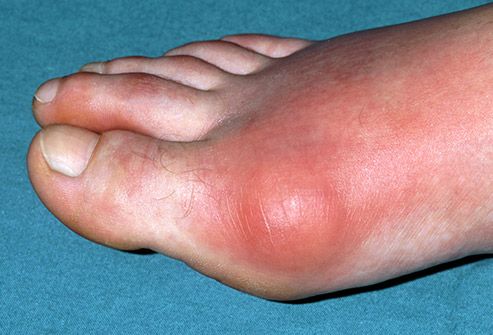

12. Bệnh Gout

Tình trạng này biểu hiện như một cơn đau và sưng đột ngột ở một trong các khớp của bạn, thường là ngón chân cái. Đây là một dạng viêm khớp do sự tích tụ của axit uric trong cơ thể bạn. Nếu bạn dùng một số loại thuốc điều trị huyết áp cao, ăn thịt đỏ và động vật có vỏ hoặc uống rượu, bạn sẽ có nguy cơ mắc bệnh cao hơn. Chất tạo ngọt trong soda có tên là fructose cũng làm tăng nguy cơ mắc bệnh và béo phì cũng vậy.